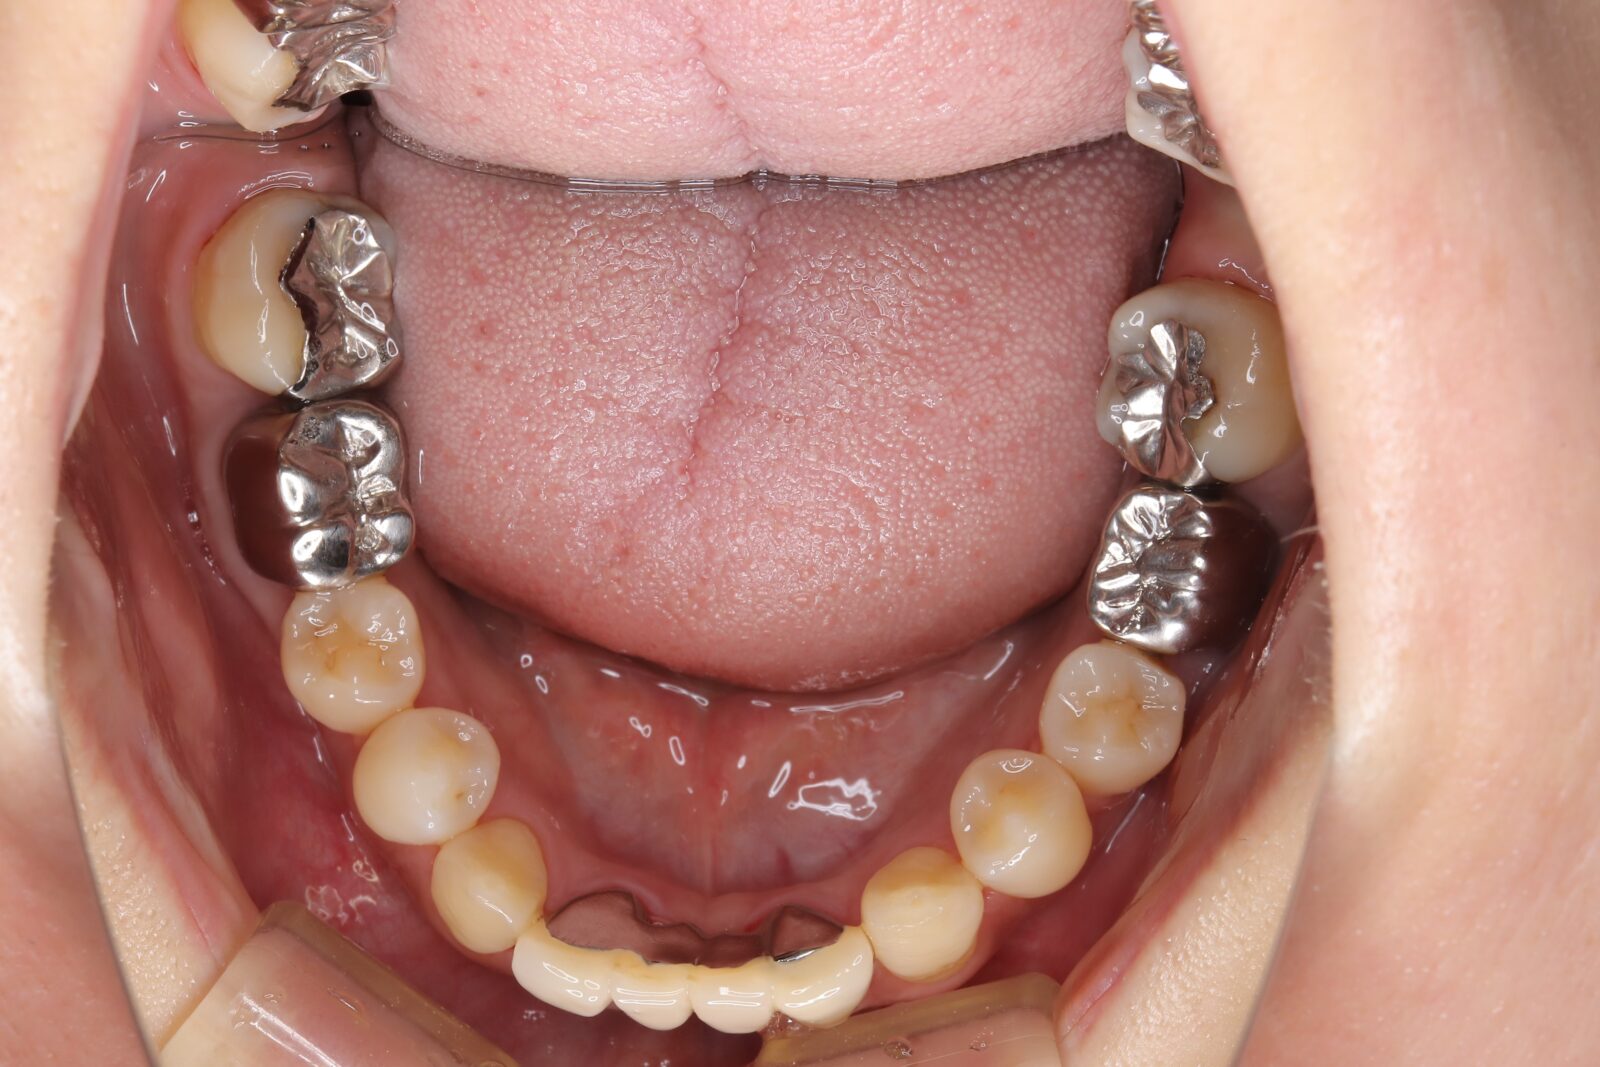

矯正と補綴が必要で実施した症例

左側に隙間。歯の数が少ない。もともと2番と7番がない。(先天欠如)歯の数が少ないため上顎のアーチ全体が小さい。歯槽骨の幅も狭く、歯肉も薄い。骨質も弱かった。

上顎左右2番と6番が先天欠如。下顎左右1番も先天欠如でもともとブリッジが装着されていた。

左右非対称なすきっ歯。上顎の前歯がないので左側の隙間を左右2番相当部に集めた。

上下の前歯が反対の噛み合わせ(受け口)で、干渉しているためうまく閉じることができず、奥歯は左右同時に噛めないので、どこかにずらさないと口を閉じられない。

左右の歯を同時に合わせることができず、どこで噛んだら良いかわからない噛み合わせでした。

小臼歯部は噛み合うことがない側方の開口状態。矯正と補綴が必要なケース。 主訴は顎の不調と歯軋り、夜間の食いしばり。

マルチブラケットとインビザラインを併用し、クラウンとブリッジを装着しました。

上顎左右2番は、歯が入るスペースを作り、ブリッジを装着しました。

他の歯医者で何軒も断られていました。 骨の幅がうすくインプラントはできない。骨の質も柔らかい。PCR検査の結果も歯周病ハイリスク患者でした。

歯の位置は、本人の顎が安定する場所を探して着地した。 左右で噛み合わせが非対称で、理想的な歯のポジションを獲得できなかったものの、左右同時に噛むことができるようになった。

顎関節の症状も落ち着いて、開口障害や、顎の痛みは無くなった。

矯正治療はどの装置を選択しても歯周病のリスクを高めてしまう。

これ以上の歯の移動が歯周病と骨質、骨の代謝のバランスの兼ね合いで困難であると判断し、ここが着地点とした。